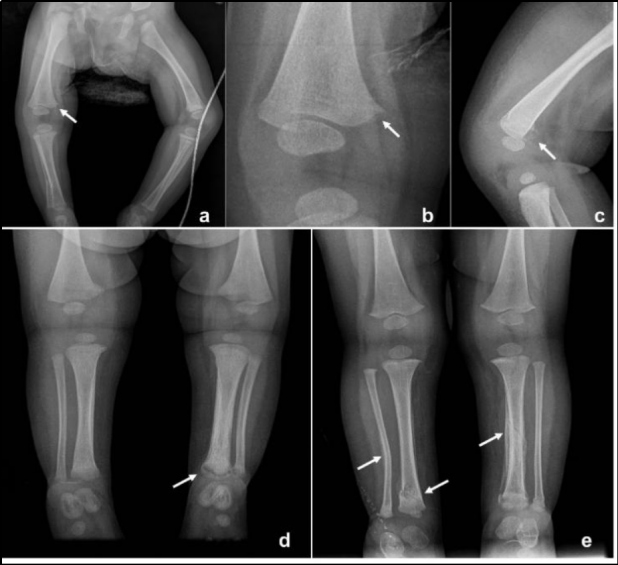

Existen muy pocos casos descritos en la literatura, y debido a su autolimitación se considera una patología subdiagnosticada, ya que su manifestación clínica es muy inespecífica. Existen dos formas de presentación(5,6): 1) La forma clásica infantil, cuya afectación suele ser asimétrica. La zona más afectada suele ser la mandíbula (70-90% de los casos), lo cual habitualmente se utiliza como criterio diagnóstico. En la mitad de los casos existe afectación clavicular, y en un 20-30% se objetiva afectación de costillas y escápulas. Tanto la epífisis como la metáfisis de los huesos largos suelen estar libres de la enfermedad. Tras la fase aguda, que tiene una duración de 1-2 semanas, le sigue una fase subaguda asintomática con cambios radiológicos (reacción subperióstica e hiperostosis con deformidades secundarias o sin ellas) que suelen persistir meses o años hasta la resolución completa sin secuelas. También es posible la recidiva(7) dando paso a una fase crónica, que rara vez deja secuelas definitivas (deformidad, acortamiento, etc.) y finaliza antes de los 2-3 años(8). Los cambios radiológicos son característicos, desarrollándose habitualmente en las tres primeras semanas. 2) La forma prenatal, más severa y mucho menos frecuente. Se caracteriza por hiperostosis ósea más extendida que en la forma clásica, angulación y acortamiento de huesos largos, polihidramnios e hidrops fetal. Este subtipo está relacionado con un alto índice de mortalidad en relación con prematuridad e hipoplasia pulmonar(5,6).

Se consideran fracturas altamente específicas de maltrato físico las costales posteriores y la lesión metafisaria clásica (fractura en esquina y en asa de balde) (Fig. 3)(10,14). Las fracturas costales en lactantes y niños pequeños se han relacionado con maltrato hasta en el 82% de los casos(11). En niños menores de 3 años, el valor predictivo positivo de las fracturas costales como indicador de maltrato es de un 95%(12).

En lactantes o niños menores de 2 años con fracturas de huesos largos, la radiografía esquelética identifica fracturas adicionales hasta en un 10% de los casos(15). Precisar el tiempo de evolución de las fracturas es fundamental en la evaluación radiológica del maltrato. La formación de hueso subperióstico ocurre generalmente entre los 7 y 10 días; el callo blando se ve entre los 10 y los 14 días y la formación de callo duro entre los 14 y 21 días(10). Cuando el patrón de curación no concuerda con la historia aportada por los adultos, se debería considerar la posibilidad de maltrato (13,15).